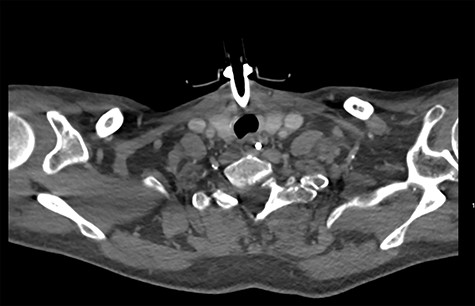

On diagnosing the right VCP, the original trauma series was reviewed by a consultant radiologist who identified a haematoma of the right carotid sheath in the neck (Fig. 1). A second CT scan of the neck and thorax was performed to determine the cause of the VCP 20 days after admission. This did not show a cause for the VCP but did demonstrate resolution of the haematoma (Fig. 2). A second FNE demonstrated resolution of the VCP 29 days following admission.